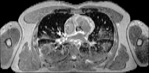

Visible Human male: Sectio transversalis 1423

CT